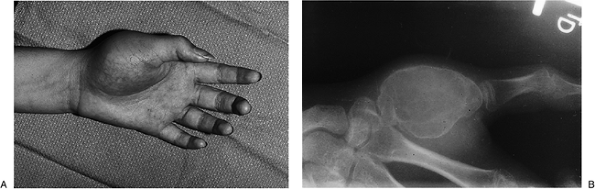

At the wrist, ganglion cysts may present as a firm, nontender mass that can be up to several centimeters in diameter (Figure 3-1). These cysts may transilluminate when a bright light source, such as a penlight, is pressed against them.

Figure 3-1 (A) View of the dorsal aspect of the right wrist, showing a large cystic mass. (B)

The mass had the characteristic appearance of a ganglion cyst and was removed, along with a suitable portion of the dorsal capsule. |